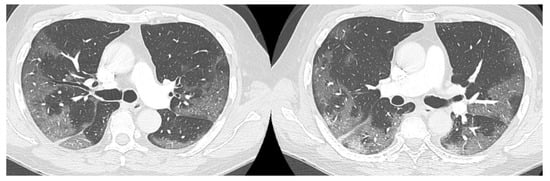

The high-resolution computed tomography scan (HRTC) made on admission (Figure 1) revealed large consolidations and bilateral ground glass opacities (GGO) areas such as progressive Covid pneumonia scored with 11/20 on Total severity score (TSS) [7].

Figure 1. HRTC performed on admission with large consolidations and bilateral ground glass opacities (GGO) TSS 11/20.